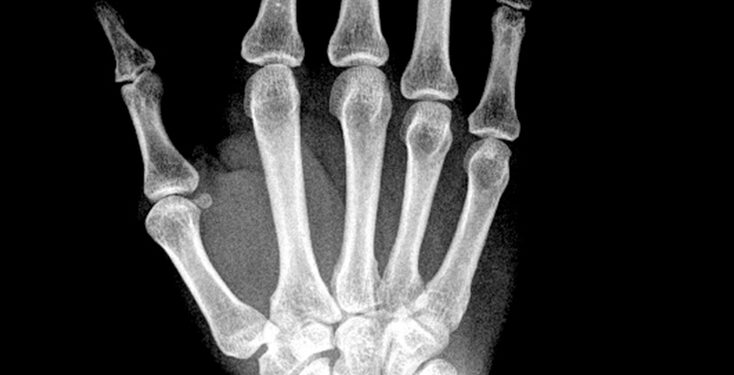

Ligos pavadinimas kilęs iš graikų kalbos žodžių – „melos“ (galūnė), „rheos“ (tekėjimas) ir „ostosis“ (kaulo formavimasis). Ši liga dar vadinama ir Leri liga. Medicininiuose vaizduose, ypač rentgeno nuotraukose, pažeistas kaulas primena tekančio vaško lašėjimą – ši išskirtinė savybė padeda gydytojams nustatyti diagnozę.

Norint patvirtinti meloreostozės diagnozę, gydytojai taiko įvairius tyrimus. Pirmiausia atliekamas rentgeno tyrimas, kuris leidžia pamatyti būdingą „varvančio vaško“ vaizdą ant pažeisto kaulo paviršiaus.